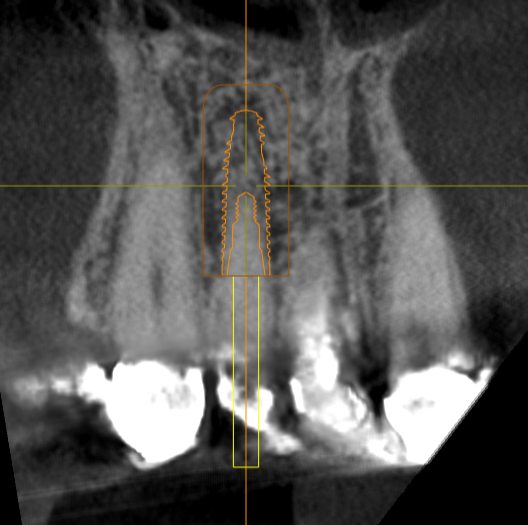

Immediate #7

Thoughts on angulation, depth, F/L position? I feel like its too deep, but wanted to at least be bone level on the lingual. Use his old crown as a temp if I achieve enough torque?

Could tip apical lingually and go cementable

In planned position, the apical third awfully close to the cortical plate.

This is a 3.75 x 13. Will be placing a 3.5 x 13

This is a neodent Helix aqua. Was curious about a 3.3 Roxolid using smile in a box as well. The last time I did this, I lost quite a bit of buccal plate.